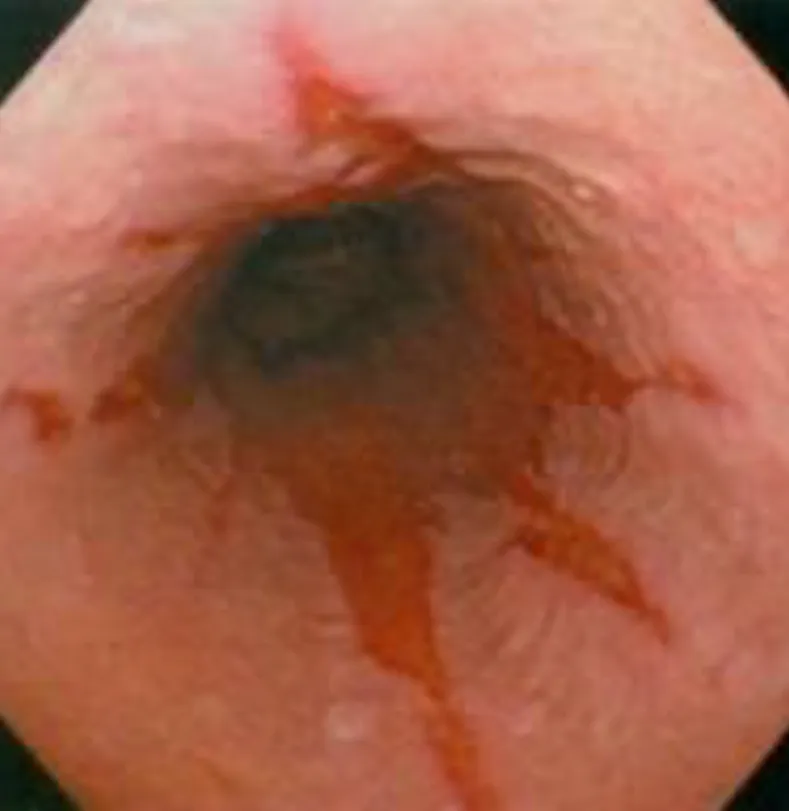

【114-2 醫學(三) 第16題】55 歲肥胖男性因為胃酸逆流、胸口灼熱接受胃鏡檢查,結果如圖。下列敘述何者錯誤?

詳解

破題關鍵

這張胃鏡影像顯示食道黏膜有發炎和線狀糜爛,這是典型的逆流性食道炎,而題目問的是關於此疾病的「錯誤」敘述,關鍵在於辨識逆流性食道炎相關的癌症風險類型。

選項拆解

-A:減重有助症狀控制。正確。肥胖會增加腹內壓,加重胃食道逆流,因此減重是改善症狀的重要生活型態調整。